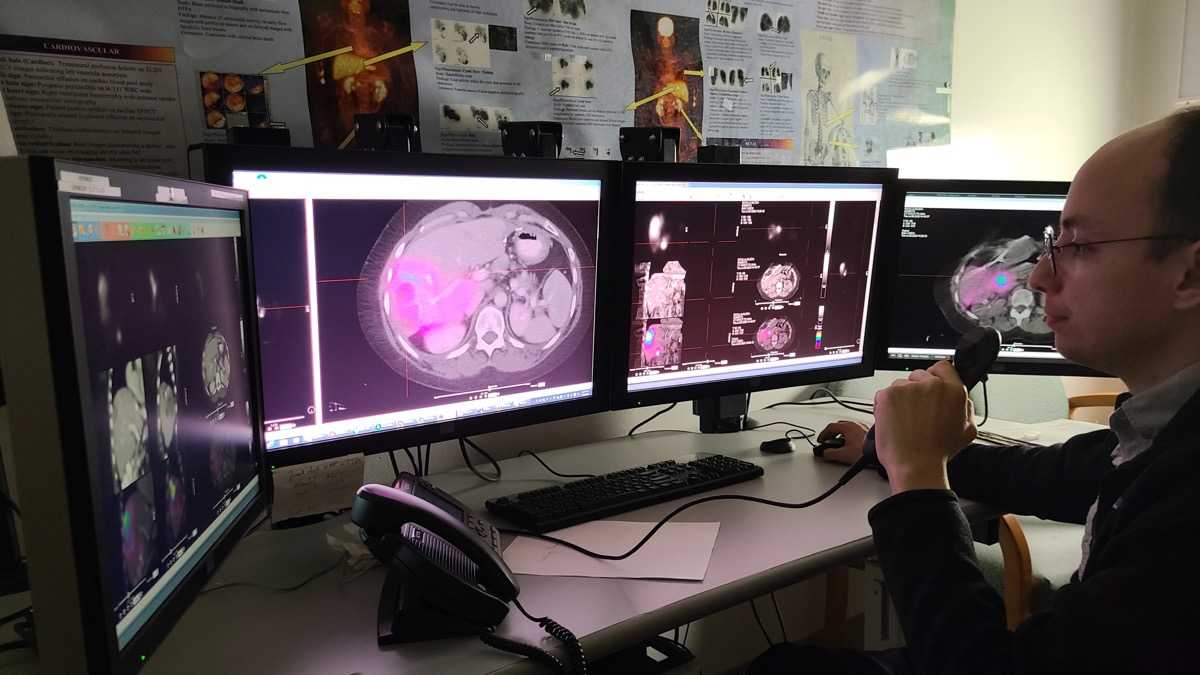

Moses Campus, along with Children’s Hospital at Montefiore Einstein, features 726 adult inpatient beds and 106 pediatric inpatient beds. The facility also offers services to outpatients. As an NCI-Designated Cancer Center, Moses provides diagnostic and therapeutic modalities through an active theranostics program. While training at Moses, residents partake in a particularly rigorous program in oncologic and non-oncologic pediatric and adult nuclear medicine. Our Transplant Center, also on-site, affords residents the ability to evaluate organ physiology pre- and post-transplant.

Our 431-bed Jack D. Weiler Hospital is located adjacent to the Albert Einstein College of Medicine in the Morris Park section of the Bronx. While at Weiler, residents participate in independent, hands-on training, with a particular focus on emergency cases and nuclear cardiology studies overseen by an attending. Residents are also exposed to much of their on-call experience at this location.

An unmatched diversity of experience